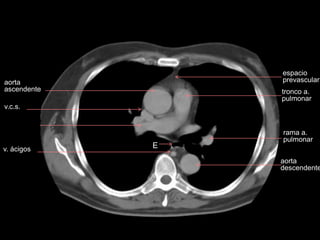

espacio

prevascular

aorta

ascendente

a. pulmonar

izquierda

descendente

v.c.s.

br. derecho

rama a.

pulmonar

tronco a.

pumonar